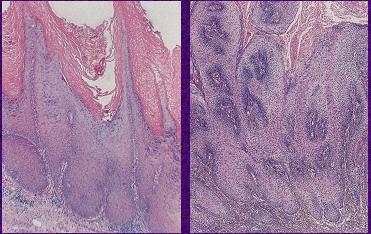

Spinocelulární karcinom